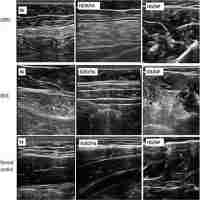

| Abstract | Oculopharyngeal muscular dystrophy is a localized or restricted variety of muscular dystrophy, characterized by bilateral ptosis, myopathic facies, external ophthalmoplegia and dysphagia. A patient with this unusual myopathy is described and detailed esophageal motility studies are presented that provide conclusive evidence of both striated and smooth muscle involvement. |